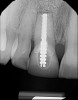

A 56-year-old female patient was referred for the evaluation of tooth No. 8 (Figure 4 and Figure 5). A periapical radiograph indicated that the tooth had undergone apicoectomy and received an excessively long post (Figure 6), and a cone-beam computed tomography (CBCT) scan of the site revealed a lack of buccal plate bone (Figure 7).

(6.) Pretreatment periapical radiograph.

Figure 6

(21.) Postoperative periapical radiograph taken immediately after placement of the implant at site No. 8 demonstrating implant positioning centered with the planned location of the gingival zenith and two titanium alloy tacks that were used to stabilize the resorbable membrane apically.

Figure 21